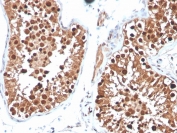

Inhibin alpha Antibody Mouse Monoclonal INHA/4265 IHC staining of human testis. Immunohistochemistry analysis of FFPE human testis tissue using Inhibin alpha Antibody Mouse Monoclonal INHA/4265 shows HRP-DAB brown cytoplasmic staining in cells within seminiferous tubules, consistent with Inhibin subunit alpha (INHA) expression in Sertoli cell populations, while surrounding stromal elements remain largely negative. HIER: tissue sections were boiled in pH 9 10mM Tris with 1mM EDTA for 20 minutes and allowed to cool before testing.

Inhibin alpha Antibody Mouse Monoclonal INHA/4265 IHC staining of human testis. Immunohistochemistry analysis of FFPE human testis tissue using Inhibin alpha Antibody Mouse Monoclonal INHA/4265 shows HRP-DAB brown cytoplasmic staining in cells within seminiferous tubules, consistent with Inhibin subunit alpha (INHA) expression in Sertoli cell populations, while surrounding stromal cells remain largely negative. HIER: tissue sections were boiled in pH 9 10mM Tris with 1mM EDTA for 20 minutes and allowed to cool before testing.